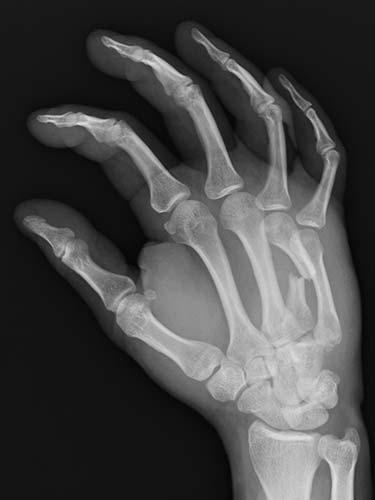

31 year old that suffered a broken bone in his hand while at work. Attempts were not possible at treating the patient without surgery because of the need to use his hand to help out with family obligations. He chose to have the hand treated with temporary wires that allowed him to help out with family obligations. The patient healed without any problems having regained full use of his hand.

- Before